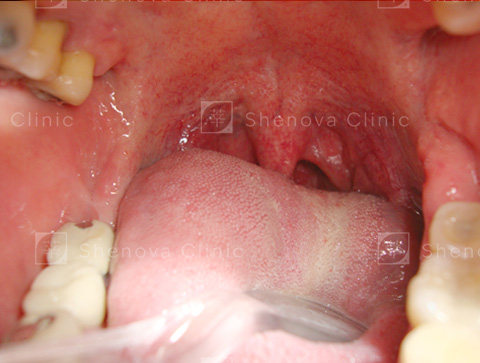

第三級_軟硬顎、扁桃腺、懸壅垂位置圖04

等級三

只可見軟顎。